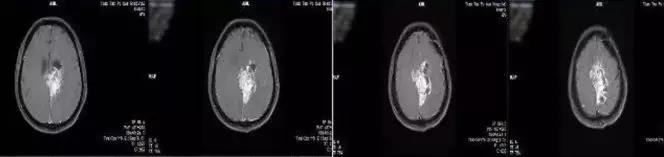

治疗前

治疗一个月后复查,病情缓解